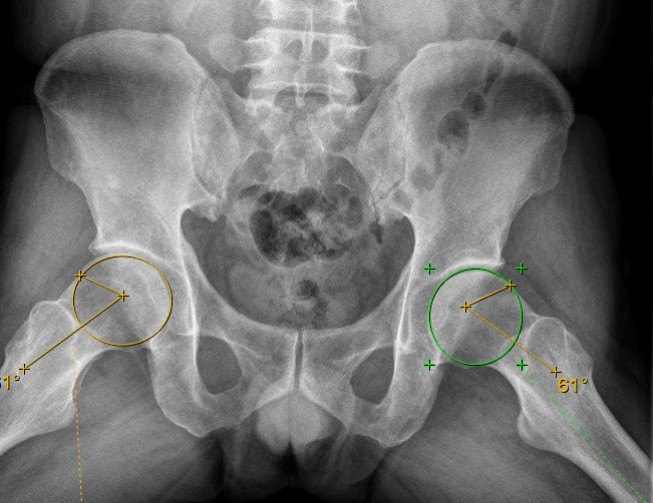

术前X骨盆正位+蛙式位提示CE角和a角增大,股骨头颈区硬化增生符合撞击表现

病史+体征+影像学 ---诊断髋关节撞击(FAI),左侧症状严重故在全麻下先行左侧髋关节镜探查+关节盂唇修复+Cam成型+关节清理。